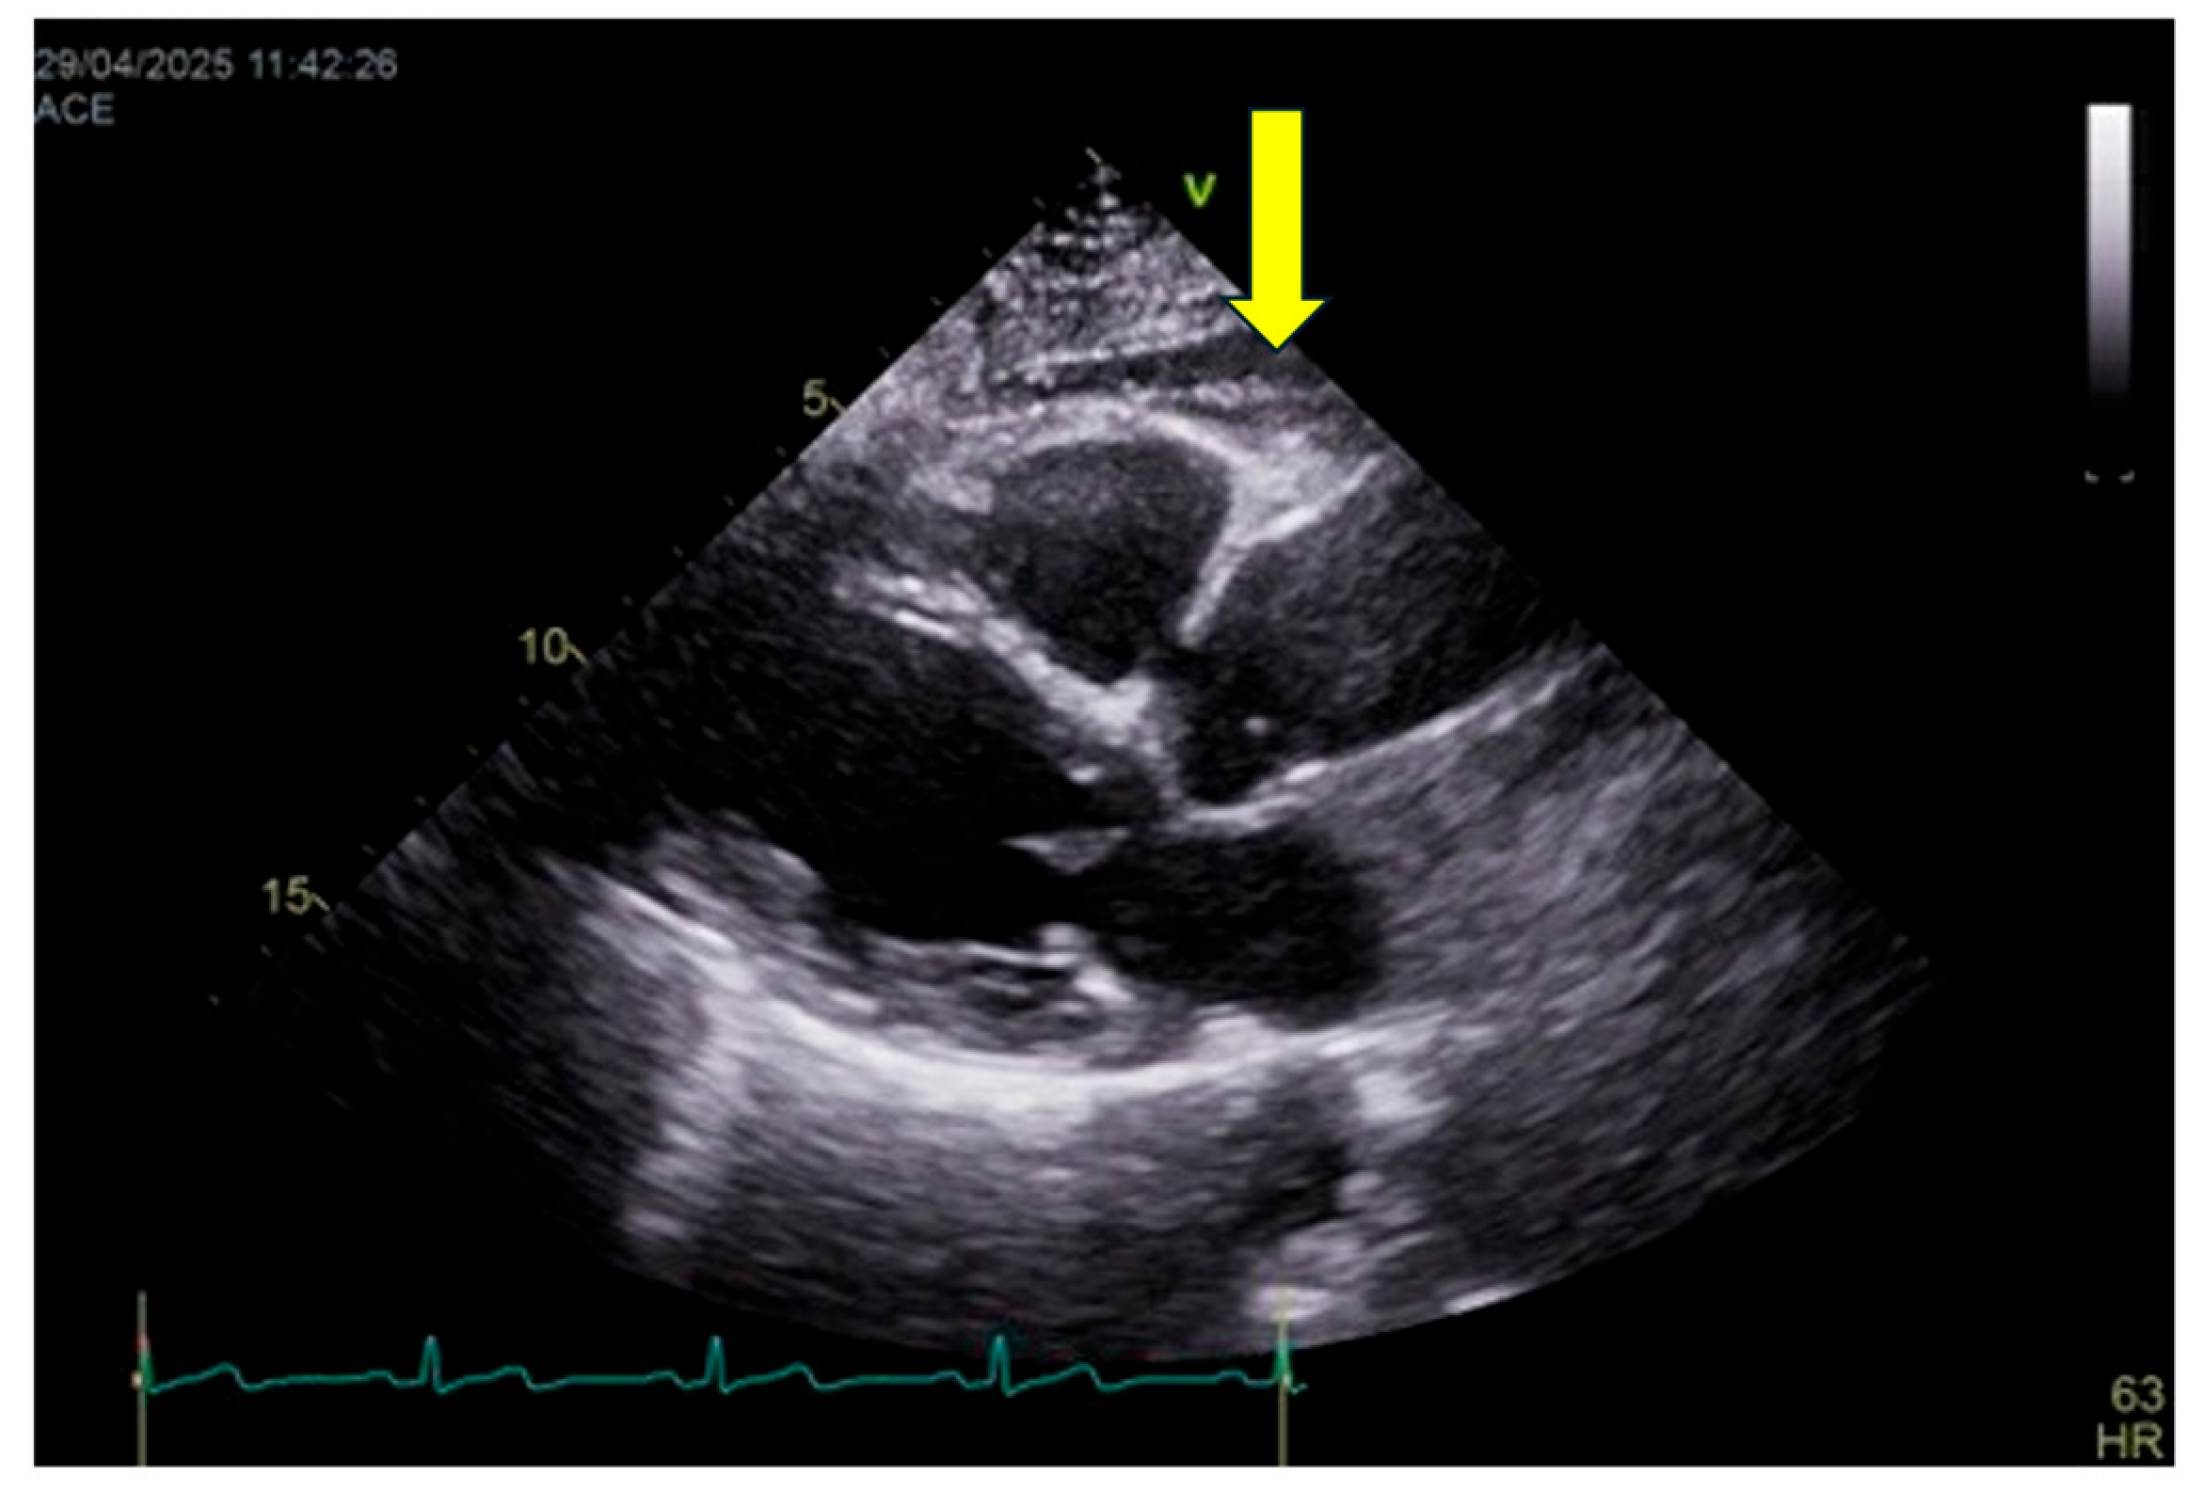

6.6.2. Measurement Protocol

EAT thickness is assessed primarily by transthoracic echocardiography (Figure 3), which represents the most practical and widely available imaging modality for routine clinical evaluation and longitudinal follow-up. EAT is measured as the echo-lucent space between the outer myocardial wall and the visceral pericardium, most commonly on the right ventricular free wall using parasternal long-axis and short-axis views. Measurements are obtained at end-systole—when EAT thickness is maximal—and averaged over at least three consecutive cardiac cycles.

Although computed tomography (CT) and magnetic resonance imaging (MRI) allow accurate volumetric quantification of epicardial fat and are considered reference techniques for research purposes, they are not incorporated into the C.O.R.E. score due to limited availability, radiation exposure (for CT), higher costs, and reduced feasibility for large-scale or repeated assessments. Accordingly, volumetric cut-offs are not included in the current scoring framework.

It should be acknowledged that echocardiography provides a linear estimate and does not fully capture total epicardial fat volume. Nevertheless, several studies have demonstrated a strong correlation between echocardiographic EAT thickness and volumetric measurements obtained by CT or MRI, as well as with cardiometabolic risk and cardiovascular outcomes. Thus, echocardiography is adopted in the C.O.R.E. model as a pragmatic compromise between diagnostic accuracy and clinical applicability, while recognizing its lower spatial resolution compared with tomographic techniques.

6.6.3. Interpretation & Thresholds

Although no universally accepted cut-off exists, commonly used echocardiographic thresholds include:

• < 5 mm: minimal or physiological EAT

• 5–7 mm: moderate EAT expansion

• o 7 mm: severe EAT accumulation

These ranges have been consistently associated with increasing cardiometabolic risk, atrial arrhythmias, coronary artery disease, and HFpEF. While CT-based volumetric thresholds (e.g., >125 mL) have been linked to elevated risk, they are reported here for contextual reference only and are not used for scoring.

In the C.O.R.E. framework, EAT contributes as a negative (penalty) domain, reflecting structural cardiometabolic burden:

• 0 points penalty: EAT < 5 mm → minimal structural burden

• −10 points: EAT 5–7 mm → moderate epicardial adiposity

• −20 points: EAT > 7 mm → severe epicardial adiposity

6.6.4. Clinical Meaning

EAT is a particularly valuable marker in individuals who otherwise appear metabolically stable based on traditional parameters. Increased EAT can be present even when glucose, lipid profiles, and blood pressure are within normal ranges, frequently identifying TOFI (thin-outside–fat-inside) phenotypes and metabolically unhealthy normal-weight individuals. Elevated EAT burden correlates strongly with atrial fibrillation, coronary artery disease, ventricular remodeling, HFpEF, and systemic inflammatory activation, providing incremental risk information beyond BMI and waist circumference [36,37,44,45].